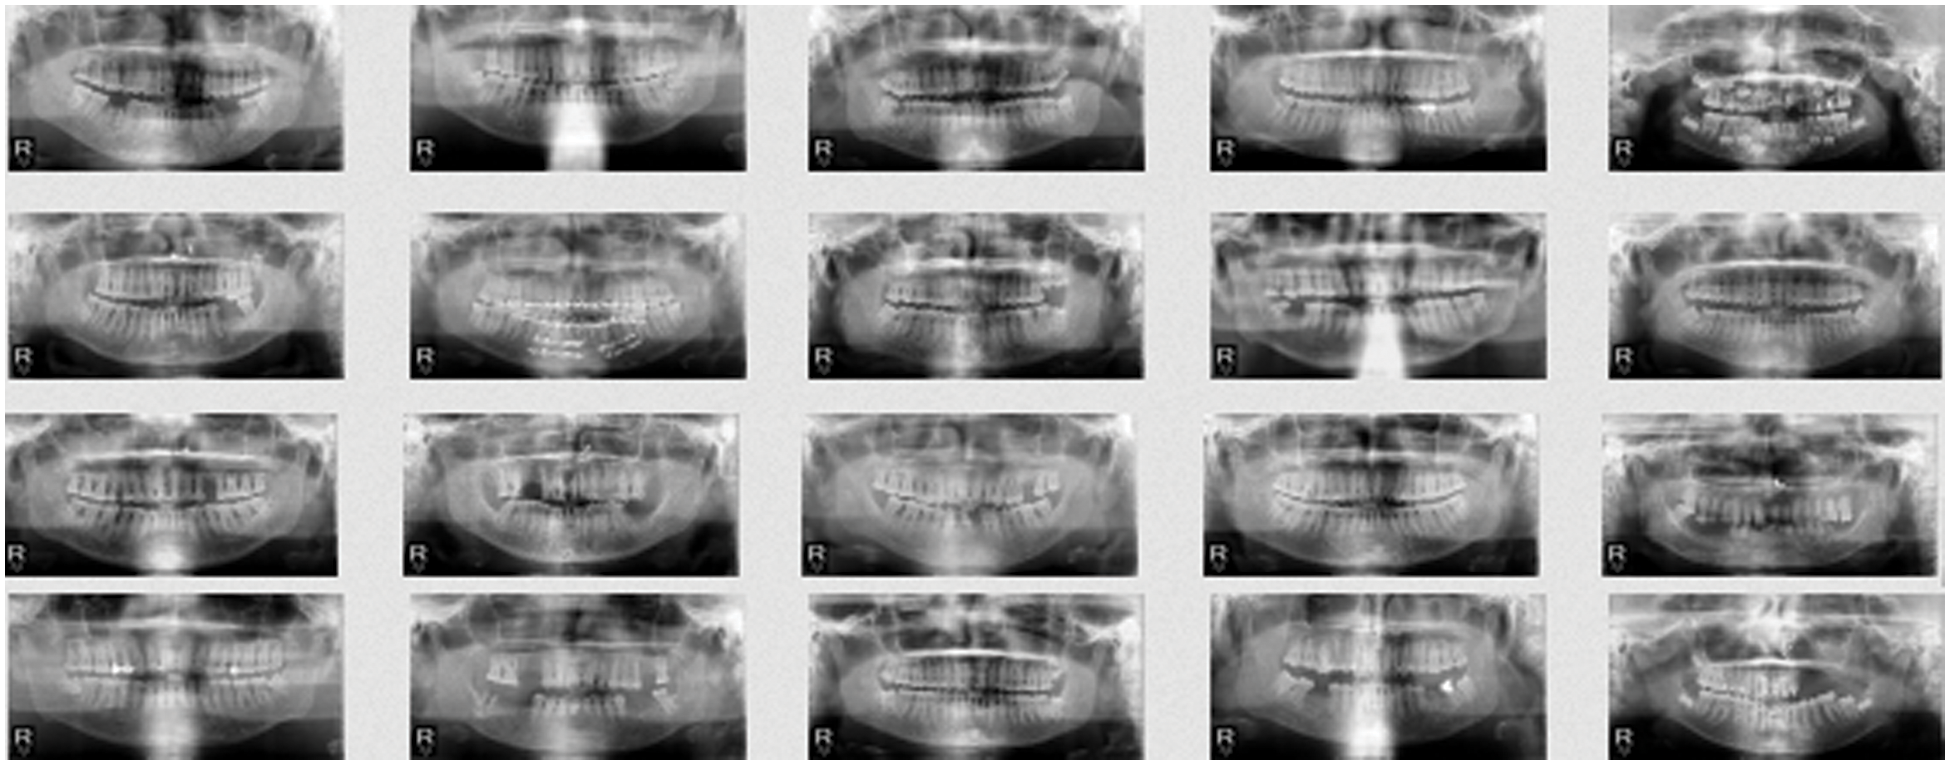

We used the mini batch stochastic gradient descent training of GANs. This technique differs from the gradient descent algorithm in the sense that it splits the training data into small batches to calculate the model errors and update the model coefficients. The algorithm of our training is detailed below, where k is a hyper parameter that states the number of steps to apply to our discriminator. After training, we generated 1000 images. A comparison between the real samples and the generated samples can be seen from Figs. 8 and 9.

Figure 8: Sample of real images